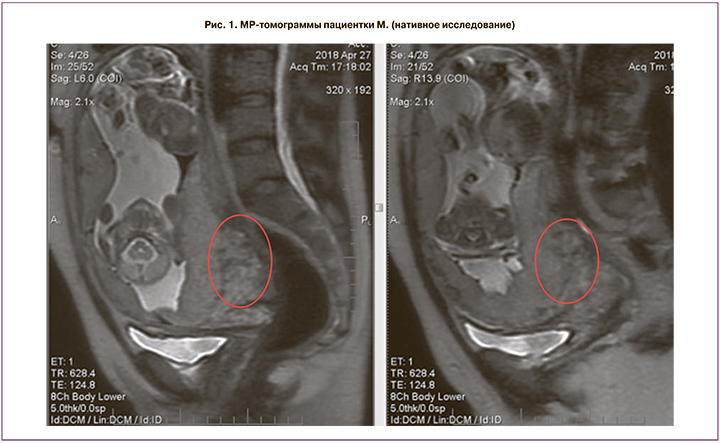

Проведено полное клинико-лабораторное исследование, по данным которого подтверждено центральное предлежание плаценты 1-го плода с признаками глубокой инвазии плацентарной ткани в ткани задней стенки матки, шейки матки и цервикальный канал (рис. 1).

МРТ-исследование органов малого таза и плода в 3 ортогональных проекциях выполнено в режимах t1 w; t1 firm; t2 w, fiesta, lava, mrcp, DWI ИП (нативное исследование) на 19–20-й неделе беременности. В полости матки определяется дихориальная диамниотическая двойня. Плацента 2-го плода расположена по передней стенке. Плацента 1-го плода расположена по задней стенке и в области внутреннего зева, полностью его перекрывает. Определяется значительное утолщение задней стенки матки и смежного отдела стенки шейки матки (до 47 мм). В толще стенки матки определяются множественные извитые и расширенные тонкостенные сосуды. Общий размер патологически измененного участка стенки матки и шейки 83×50×86 мм. Контуры прилежащей части плаценты неровные, местами нечеткие и прерывистые. МРТ-картина предлежания плаценты 1-го плода с признаками врастания.